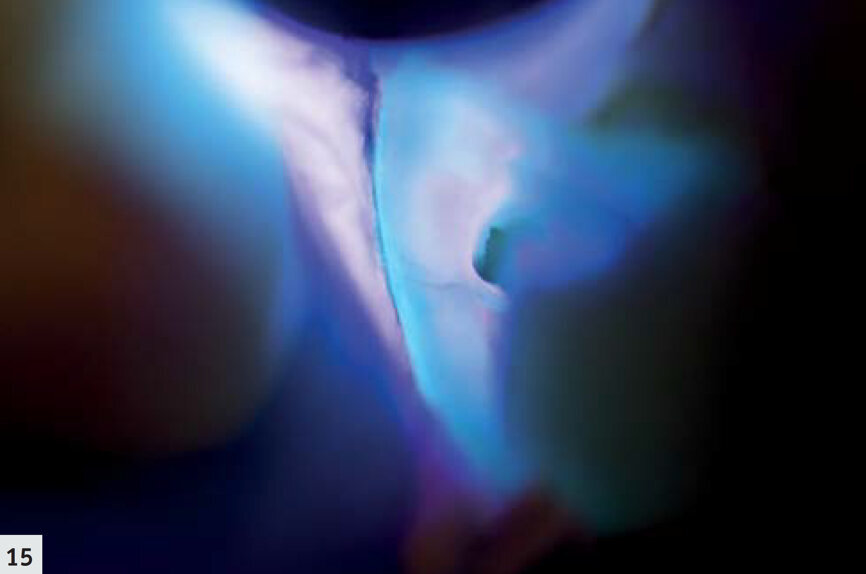

Fig: 15 : Vue rapprochée d’une limite marginale de la restauration. Un petit espace est visible sous forme d’une ligne violette, adjacente à la restauration fluorescente bleuâtre.

La majorité des résines composites émettent une hyperfluorescence sous le rayonnement proche-UV.6, 7 Les autres restaurations, minimes, peuvent facilement être observées en mode détection (Fig. 14). De cette façon, il est possible de déceler la présence d’un surplomb et de définir plus aisément les espaces marginaux (Fig. 15). L’élimination des restaurations défectueuses devient ainsi beaucoup plus facile et s’effectue sans retrait inutile de tissu dentaire sain. De plus, ce mode représente un outil très utile au cours des techniques de scellement ; les excès de ciment résine sont immédiatement détectés et peuvent donc être éliminés (Fig. 16) sans polymérisation simultanée ; après le nettoyage, le même dispositif peut être utilisé pour polymériser les limites marginales (Fig. 17). Au cours du suivi, les restaurations sont mieux visualisées (Figs. 18–19) et il est possible d’examiner rapidement et complètement leurs limites marginales.